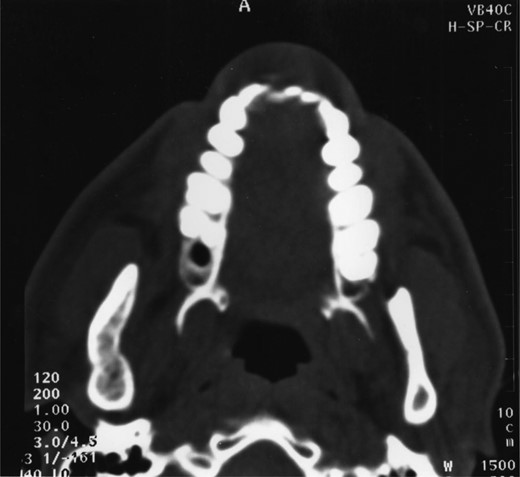

A 25-year-old man presented with a 2-month history of facial pain and limited mouth opening associated with a 3-week history of swelling of the right cheek. Radiographic analysis revealed a loculated, fluid-filled, well-demarcated lesion destroying and expanding the ascending ramus, extending out into the soft tissues, from the condyle down to the angle (Fig. 1).

A well-demarcated lesion extending out into the soft tissues from the ramus of the mandible.